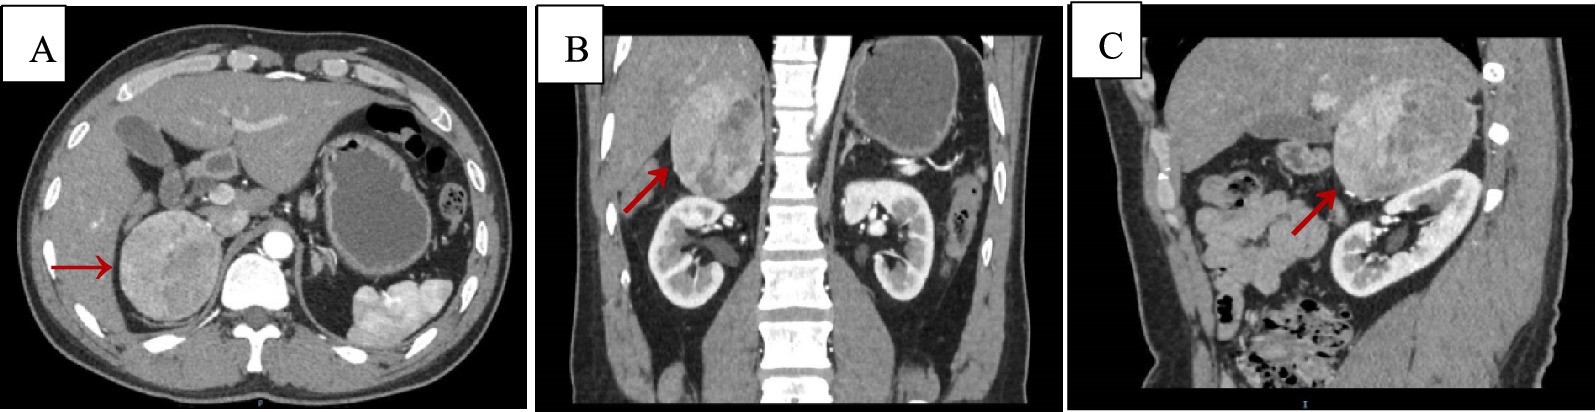

Upon admission, routine blood tests indicated a hemoglobin level of 93 g/L, and no abnormalities were found in adrenal-related hormones and residual tests. Adrenal CT + CT angiography showed a slightly lower density mass in the right adrenal gland, with a clear boundary, measuring approximately 6.6 cm × 5.2 cm × 7.0 cm, and a CT value of 34 HU (Figure 1).

Figure 1. Adrenal CT + CTA scan, arterial phase images. Axial (A), coronal (B), and sagittal (C) views demonstrating a suprarenal mass measuring 6.6 cm × 5.2 cm × 7.0 cm, with a CT value of approximately 34 Hu (red arrows).